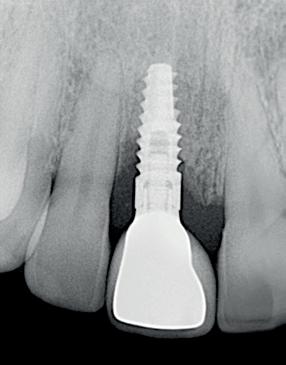

Implantologische behandelingen in het esthetische front vragen meer dan technische vaardigheid alleen. Ze vragen om overzicht, timing, vertrouwen en een team dat als vanzelf samenwerkt onder druk. Juist bij complexe casussen, waarin angst, infectie en hoge esthetische verwachtingen samenkomen, wordt zichtbaar hoe bepalend de rol van de tandartsassistent is.

Deze casus beschrijft een uitgebreide immediate implantaatbehandeling bij een patiënt die door meerdere collega’s werd geweigerd. Niet omdat de mogelijkheden ontbraken, maar omdat de complexiteit vroeg om een perfect afgestemde samenwerking. Het verhaal laat zien hoe de assistent in zo’n traject veel meer is dan een uitvoerende kracht of “mal”, maar een dynamische surgical guide die het proces mede stuurt, bewaakt en mogelijk maakt.De patiënt: wanneer alles samenkomt

Na het klinische onderzoek volgde het röntgenologisch traject. De CBCT liet precies zien wat we al vreesden: een front waarin het bot onregelmatig was, duidelijke radiolucenties rond de pijlers en een infectiegebied dat zich onder vrijwel de gehele brug had verspreid. Tegelijkertijd was er ook potentie. Net voldoende botstructuur om immediate implantaatplaatsing te overwegen, mits alles perfect gepland zou worden.